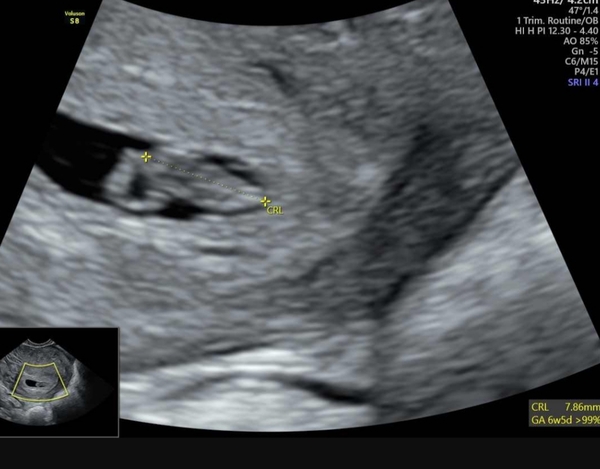

We have a heartbeat!!! Obviously still SO early (measured 6+5 so exactly what I predicted based on ovulation, I'd be 6+2 by lmp) but am so relieved. 7.86mm and the heartbeat was 'thundering' according to sonographer. Bawled my eyes out!